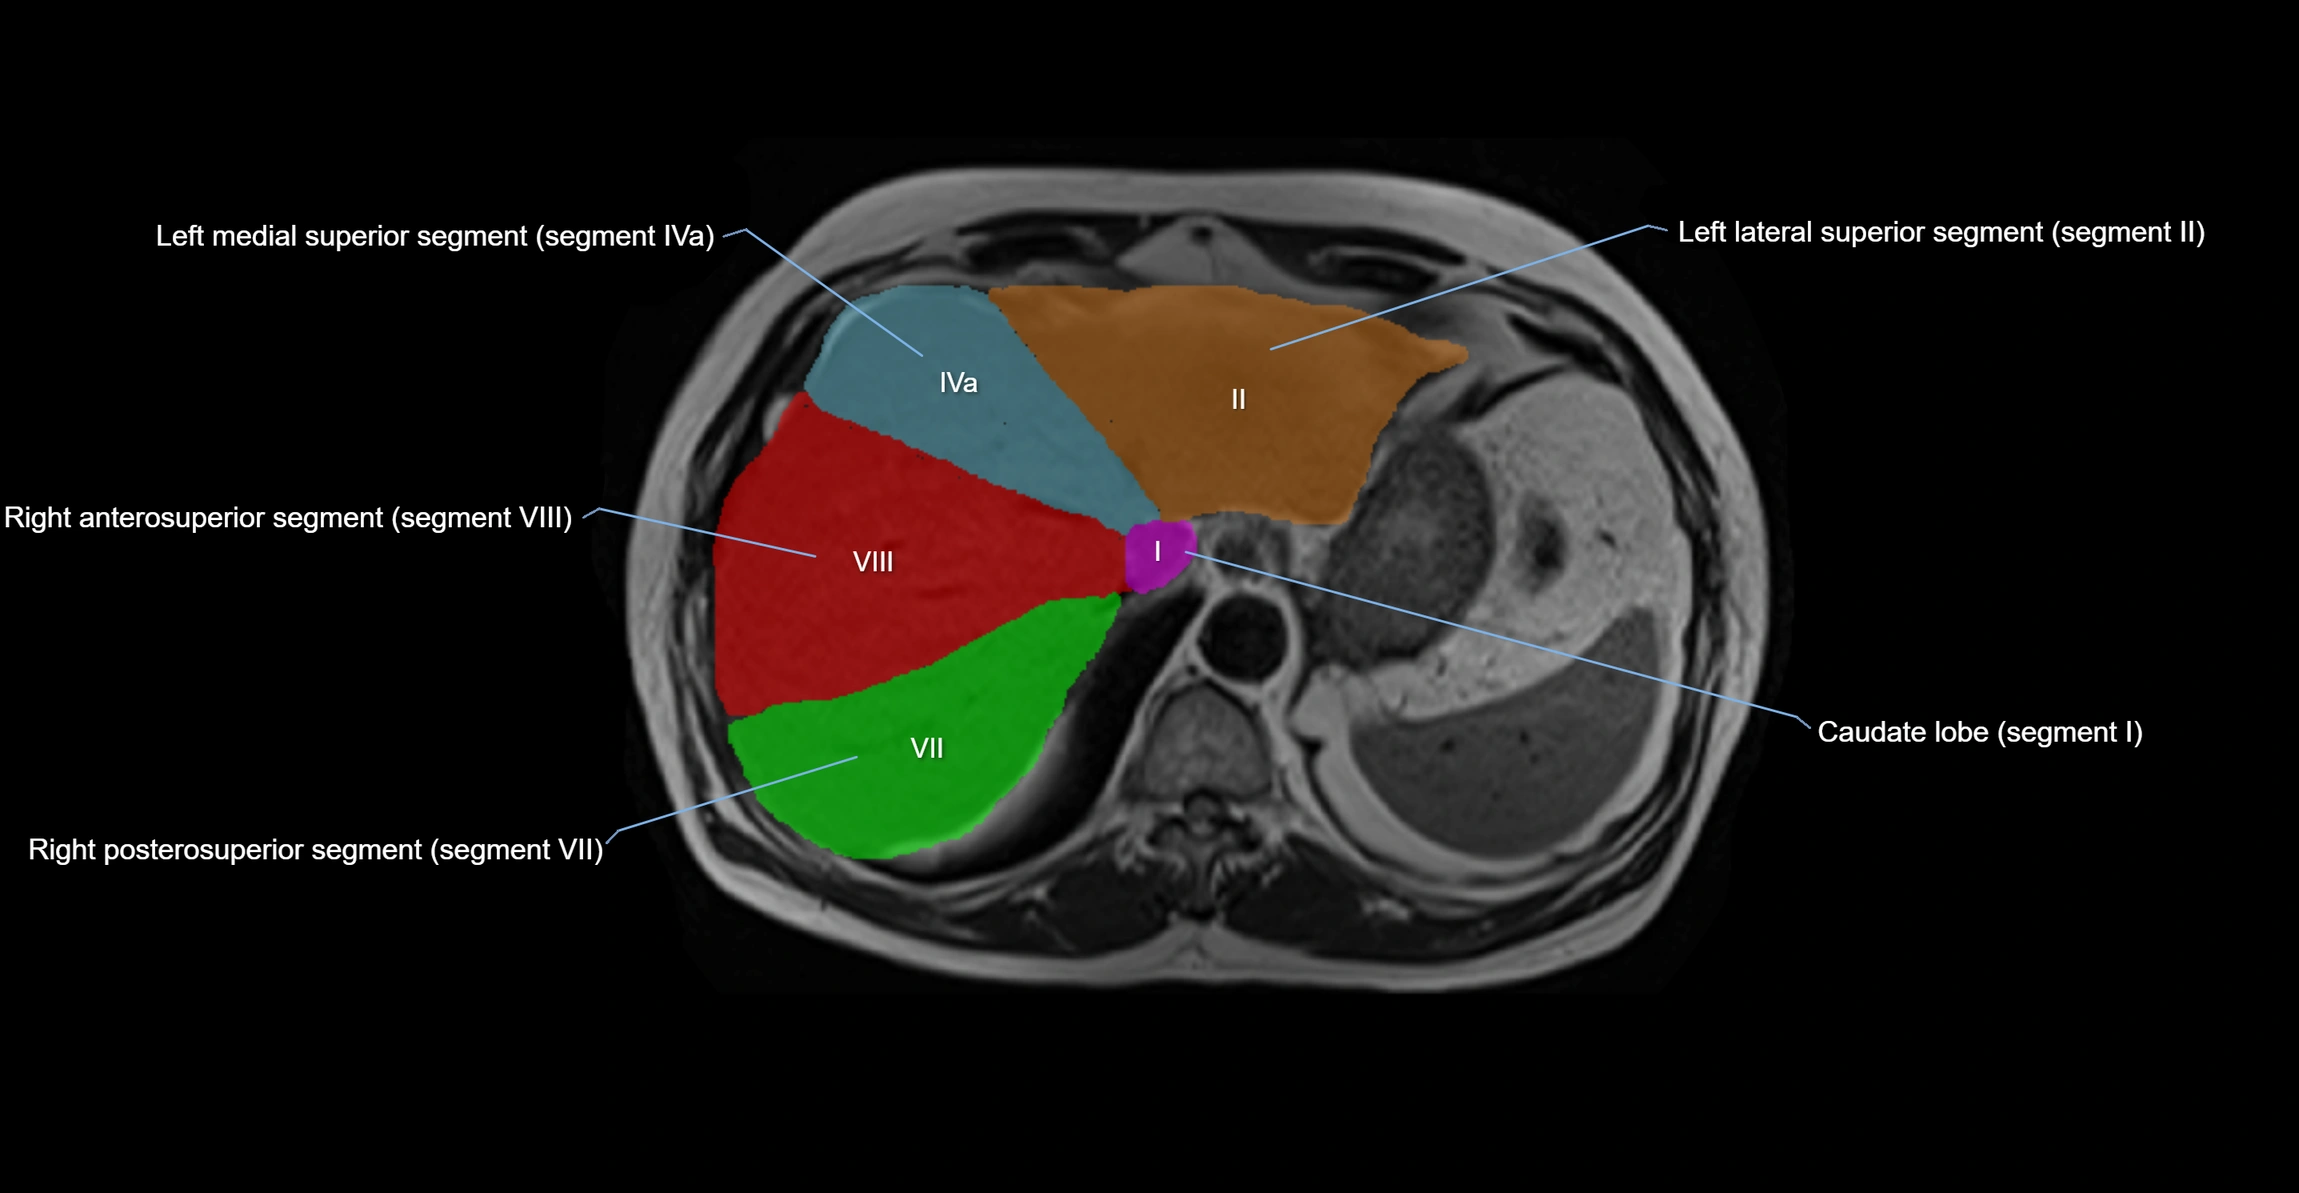

The caudate lobe of the liver is a distinct anatomical subdivision of the liver, designated as segment I in Couinaud’s classification. It lies on the posterior surface of the liver, between the fissure for the ligamentum venosum (left boundary) and the groove for the inferior vena cava (IVC) (right boundary). Superiorly, it is related to the posterior liver surface, and inferiorly it is separated from the left lobe by the porta hepatis.

The caudate lobe is unique because it receives dual portal venous and arterial inflow from both the right and left portal veins and hepatic arteries. It also has independent venous drainage directly into the IVC via multiple small hepatic veins, unlike other lobes that drain through the three main hepatic veins.

• Segment I (Couinaud classification)